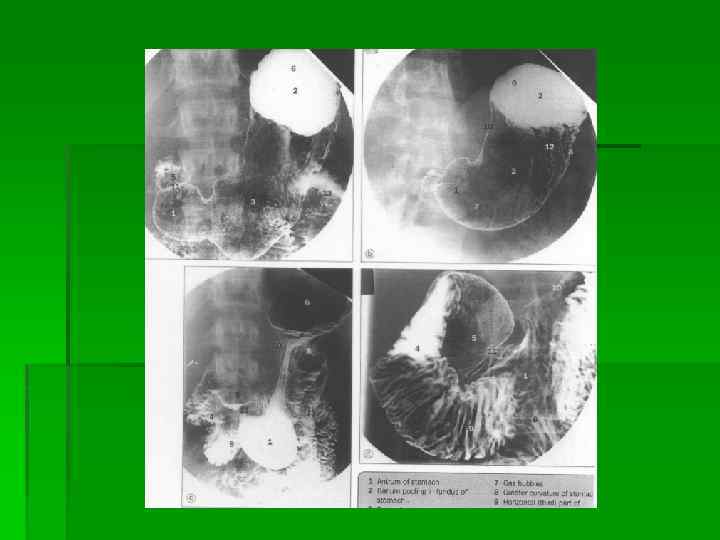

Скелетотопия желудка

Холангиография

Ирригография